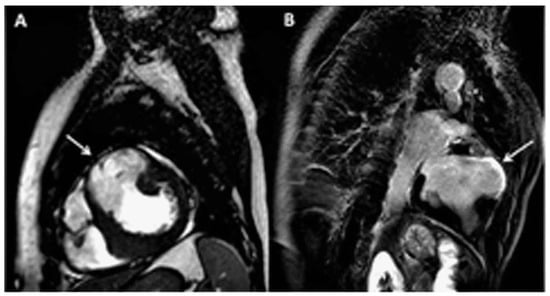

Echocardiography showed the presence of a large LV antero-lateral wall aneurysm (maximal dimensions of 57 × 41 mm) with the wall thinning resulting in the moderately depressed LV ejection fraction of 35% with preserved contractility of the remaining LV segments (Figure 1A,B, arrows). Coronary artery disease with previous silent myocardial infarction was suspected. Subsequently performed coronary angiography demonstrated normal coronary arteries.

Figure 1. Echocardiography parasternal short-axis (A) and apical two-chamber view (B) showing the presence of large left ventricular antero-lateral wall aneurysm (arrows).